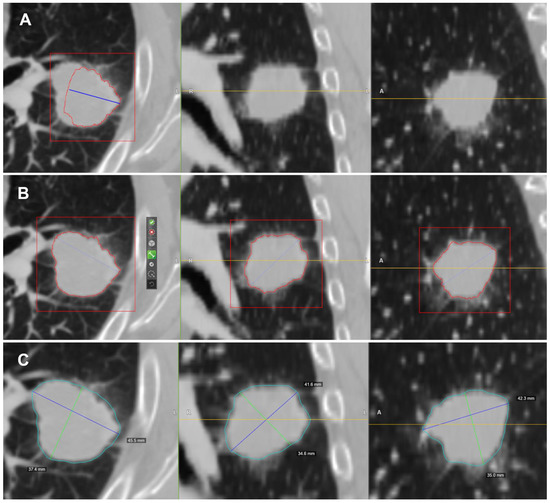

2.4. CT Post-Processing with Radiomic Precision Metrics (RPM™) Tool